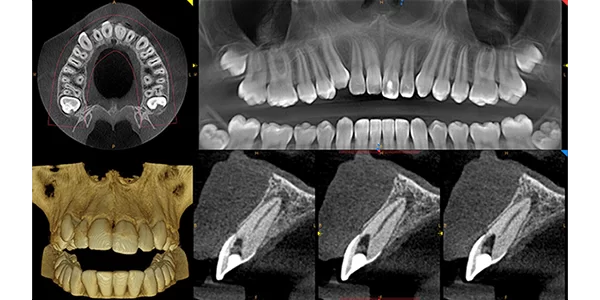

Cone Beam Computed Tomography (CBCT) is a unique type of X-Ray that allows a Dental Surgeon to see the Craniofacial structures, bone, soft tissues, and even nerve pathways of a patient, all in a 3D Image. Unlike Panoramic X-Rays which are 2 dimensional, the CBCT scan allows doctors to see buccal/Lingual distance, bone quality and surgically plan the placement of each implant.

Selectable CBCT fields of view from 5 cm x 5 cm to 17 cm x 13.5 cm.

Very low dose and superb image quality up to 90 μm resolution.